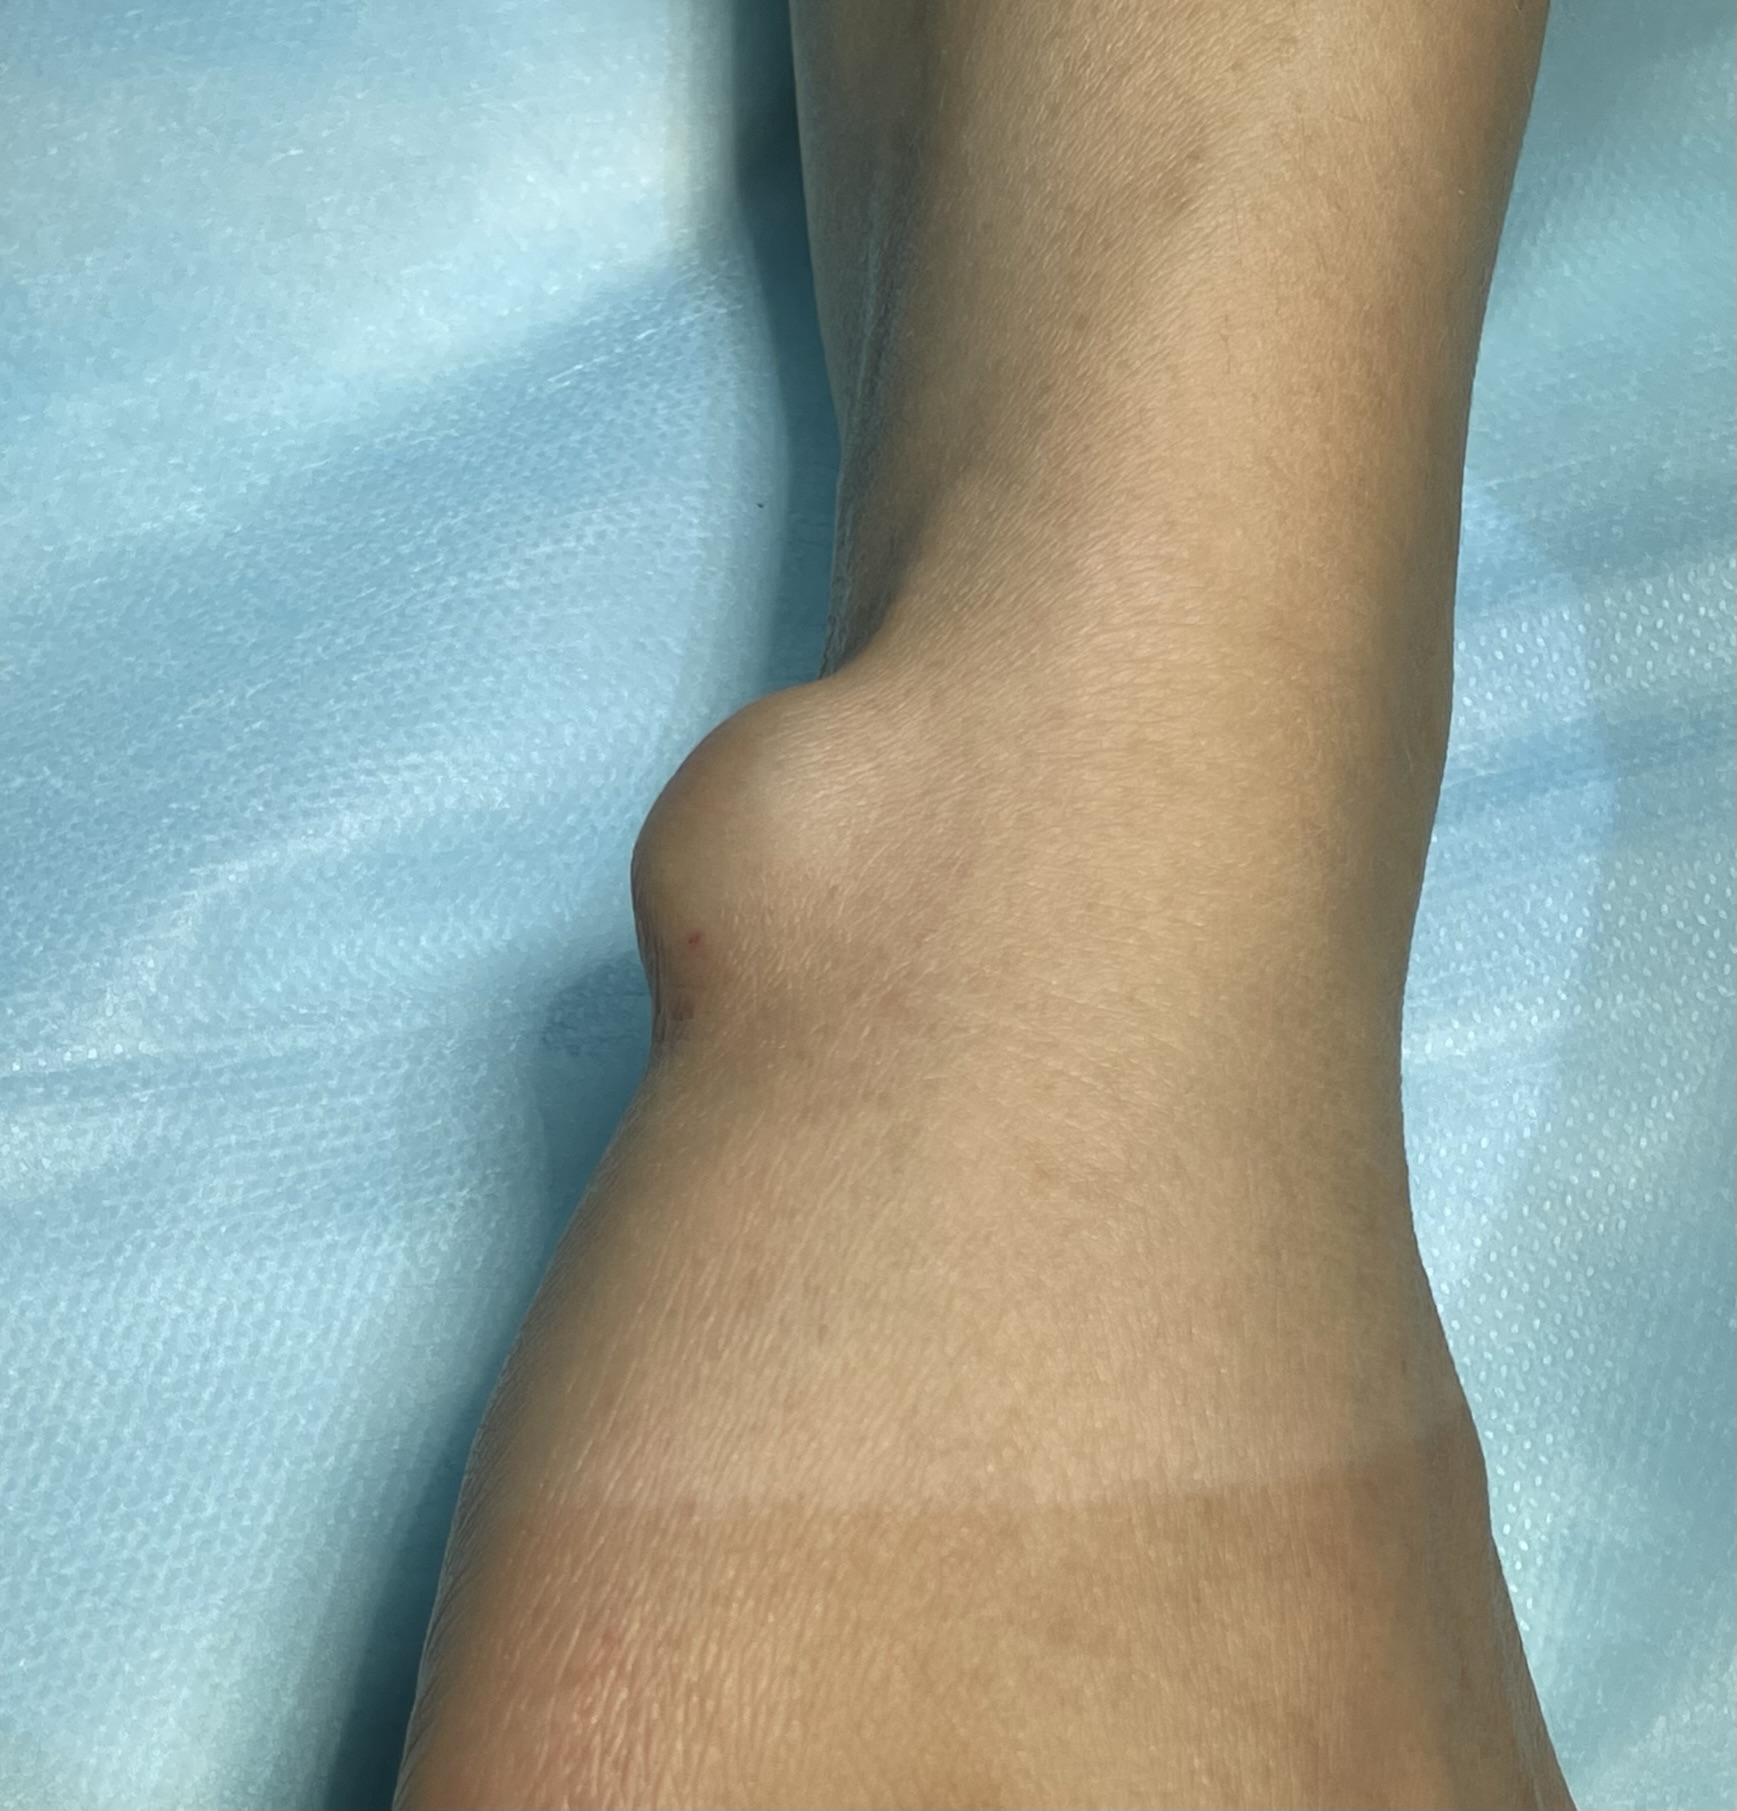

Клинический случай: тыльная гигрома запястья

Пациент с тыльной гигромой, подтверждённой на УЗИ. Выполнено хирургическое лечение, документированы этапы контроля и результаты.